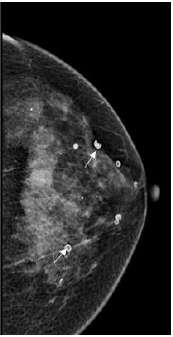

‘Tattoo Sign’- A useful sign in demonstrating the superficial location of skin calcifications. In this sign, the position of the calcifications does not change on multiple views [6] (Figure 1a & 1b).

Figure 1:a) Skin calcifications(arrows) noted in the CC FFDM and DBT view of the right breast of a 50-year-old woman. b) Digital Breast Tomosynthesis images aid in the diagnosis of skin calcifications as they are seen in the first or last three of the images in the stack. Image Courtesy: HCG Hospitals, Bangalore.